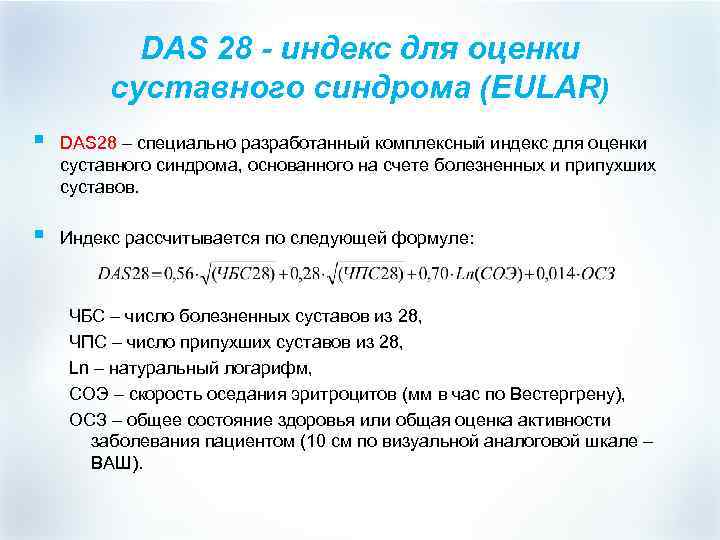

DAS 28 - индекс для оценки суставного синдрома (EULAR) § DAS 28 – специально разработанный комплексный индекс для оценки суставного синдрома, основанного на счете болезненных и припухших суставов. § Индекс рассчитывается по следующей формуле: ЧБС – число болезненных суставов из 28, ЧПС – число припухших суставов из 28, Ln – натуральный логарифм, СОЭ – скорость оседания эритроцитов (мм в час по Вестергрену), ОСЗ – общее состояние здоровья или общая оценка активности заболевания пациентом (10 см по визуальной аналоговой шкале – ВАШ).

DAS 28 - индекс для оценки суставного синдрома (EULAR) § DAS 28 – специально разработанный комплексный индекс для оценки суставного синдрома, основанного на счете болезненных и припухших суставов. § Индекс рассчитывается по следующей формуле: ЧБС – число болезненных суставов из 28, ЧПС – число припухших суставов из 28, Ln – натуральный логарифм, СОЭ – скорость оседания эритроцитов (мм в час по Вестергрену), ОСЗ – общее состояние здоровья или общая оценка активности заболевания пациентом (10 см по визуальной аналоговой шкале – ВАШ).